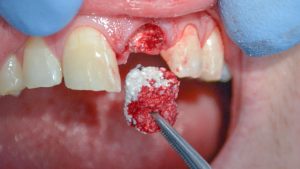

Bone grafting is a surgical procedure that involves adding bone material to your jaw to regenerate and strengthen areas where bone has deteriorated or thinned. The bone graft material used may come from your own body (autograft), a donor source (allograft), an animal source (xenograft), or synthetic materials that are biocompatible and safe.

Over time, the grafted bone integrates with your existing bone through a natural healing process called osseointegration. This provides a stable foundation for dental implants or improves the fit and comfort of dentures.